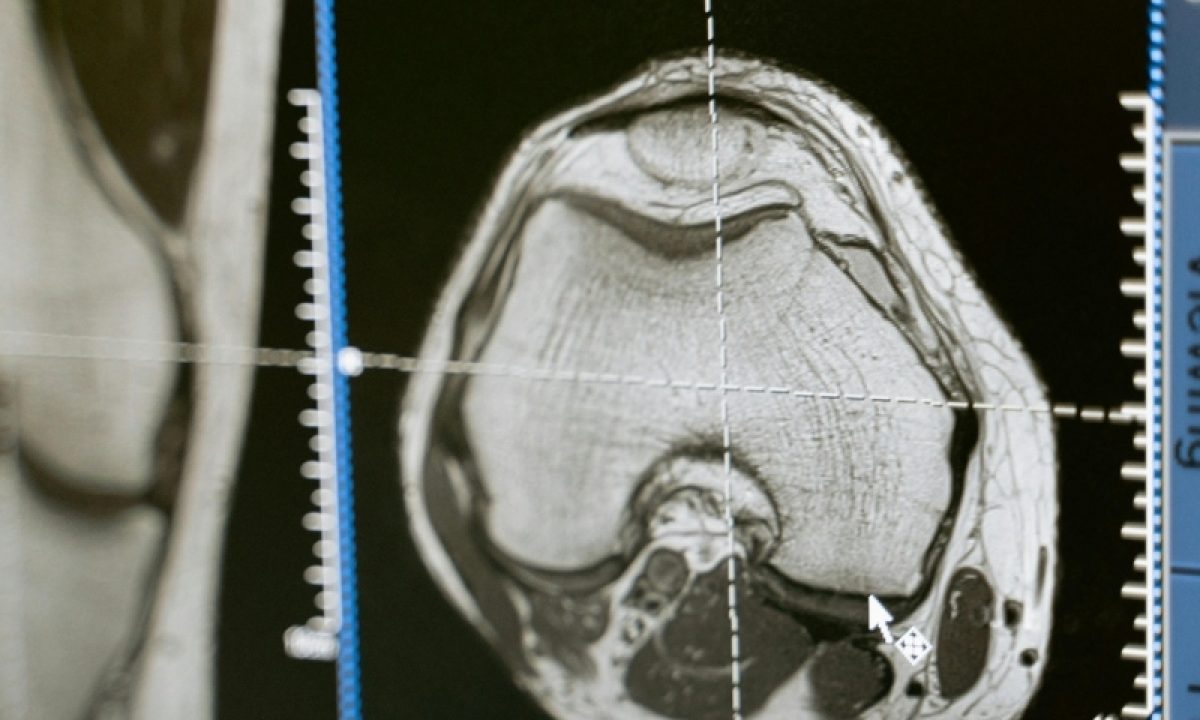

O Ministério Público de Mato Grosso do Sul (MPMS), por meio da 4ª Promotoria de Justiça de Três Lagoas, obteve resultado favorável na Justiça, representando um avanço significativo para a saúde pública em Três Lagoas. Em sentença proferida nos autos da Ação Civil Pública nº 0900776-62.2024.8.12.0021, a Justiça determinou que o Estado de Mato Grosso do Sul e o Município de Três Lagoas cumpram prazos máximos para a realização de exames de ressonância magnética, conforme a gravidade dos casos.

A ação civil pública foi protocolada pela 4ª Promotoria de Justiça de Três Lagoas, sob a titularidade da Promotora de Justiça Ana Cristina Carneiro Dias. O MPMS constatou a insuficiência na oferta de exames de ressonância magnética na macrorregião de Três Lagoas, o que tem causado longas filas de espera, inclusive em casos de urgência e emergência, o que coloca em risco a saúde e a vida da população que depende do serviço.

Segundo a ação, em 2023, eram 1,1 mil pacientes na fila à espera de exames de ressonância magnética, sendo 204 de urgência e 17 de emergência. O aumento da demanda represada de pacientes foi de 850%, mesmo com o aumento da oferta de exames.

Sendo assim, a Justiça determinou que o estado de Mato Grosso do Sul e o município de Três Lagoas elaborem e implementem, no prazo de até 180 dias, um plano de ação que assegure a realização de exames de ressonância magnética em até cem dias para casos eletivos e em até 30 dias para pacientes em emergência e urgência. Após o término desses prazos, não poderá haver pacientes aguardando em filas além dos limites estabelecidos, sob pena de aplicação de multa ou de outras medidas coercitivas.